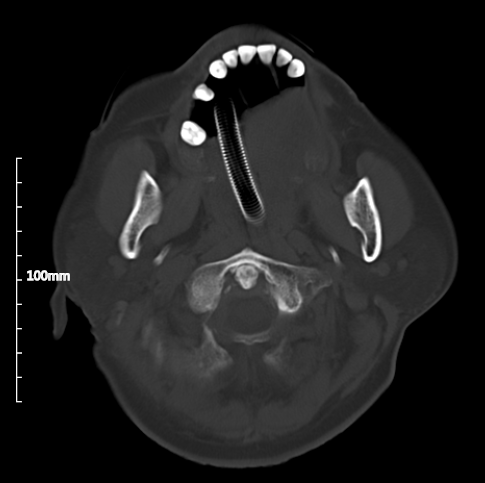

即可呈现影像: